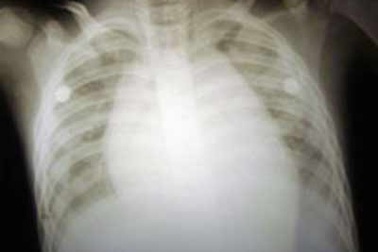

Cứu sống bệnh nhi “tí hon” bị dị dạng nang tuyếnChào đời khi mới 31 tuần tuổi với cân nặng chỉ 1,7 kilô, bé T. còn mang trong mình dị dạng nang tuyến bẩm sinh, gây suy hô hấp nặng. Để giữ lại sự sống cho cháu, các bác sĩ đã phải tiến hành phẫu thuật gấp, cắt bỏ thùy giữa phổi bên phải.